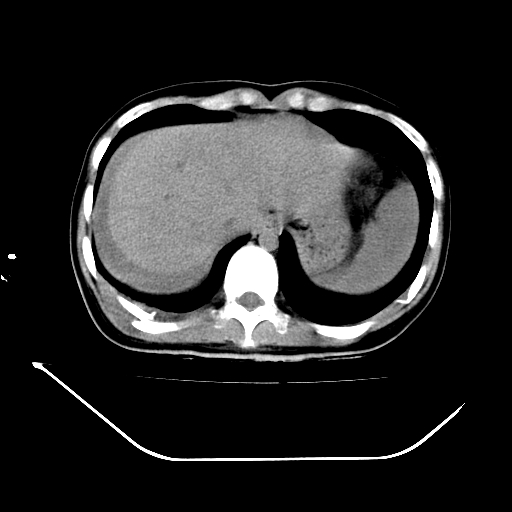

以下是引用liuyue在2008-7-19 13:02:00的发言:[br]1.肝右叶后下段及右肾挫裂伤伴腹腔积血。[br]2.右侧多发性肋骨骨折、横突骨折、右髂骨骨折伴周围软组织挫伤。[br]3.右侧腰大肌肿胀,并可见低密度影,如为气体,则肠道挫裂伤待除外。

以下是引用zhengfaming在2008-7-19 14:42:00的发言:[br]1.肝右叶后下段及右肾挫裂伤伴腹腔积血。脾脏挫裂伤待排[br]2.右侧多发性肋骨骨折、横突骨折、右髂骨骨折伴周围软组织挫伤。[br]3.右侧腰大肌肿胀,并可见低密度影,如为气体,则肠道挫裂伤待除外

以下是引用道哥在2008-7-19 16:52:00的发言:[br]肝右叶后下段及右肾挫裂伤、脾破裂伴腹腔积血。[br]2.双侧多发性肋骨骨折、横突骨折、右髂骨骨折伴周围软组织挫伤。[br]3.右侧腰大肌肿胀,并可见低密度影,如为气体,则肠道挫裂伤待除外。